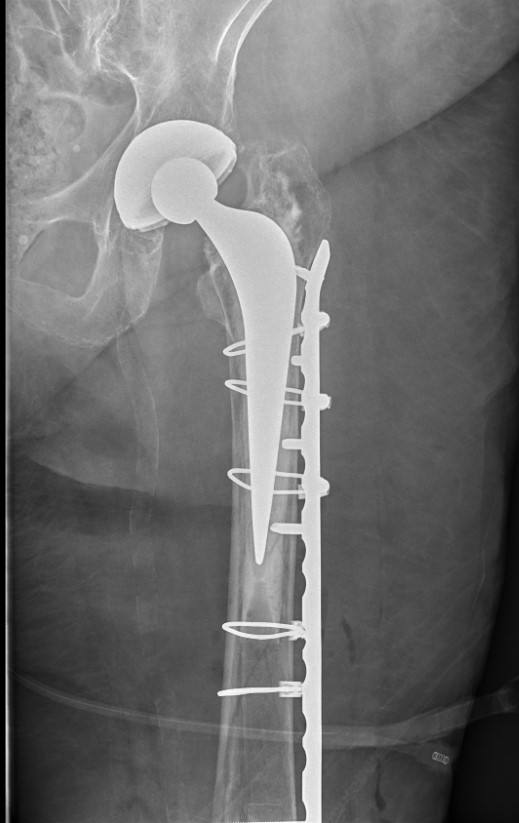

Long stem uncemented revision

Long stem uncemented revision with cortical strut allograft

Long stem uncemented revision with plate + cortical struts

Type B3: Fracture around stem with poor bone quality (osteolysis of comminution)

Options

- long stem modular revision implants +/- plate +/- cortical strut